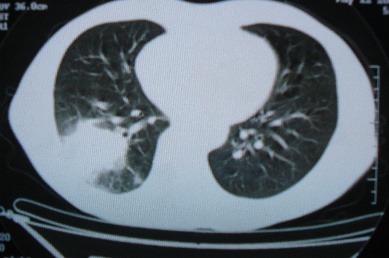

ct10716,男,59岁。发热咳嗽一天,咯血一次入院。

病灶中心有低密度,气体,病灶周围炎性浸润可能为肺脓肿,量体温、查个痰就是了,但肺脓肿一般都多少会有点兄水的。左肺下局部密度减低,小叶中心肺气肿。

病灶边缘较模糊,中心见低密度影及少量气影,宽基与胸膜相连,周围见炎性浸润,考虑右下肺脓肿。

病灶边缘较模糊,中心见低密度影及少量气影,宽基与胸膜相连,周围见炎性浸润,考虑右下肺脓肿。建议治疗后复查。

右下肺病灶,边缘模糊,中心见低密度坏死区及气体影,结合病史较短,以发热为主,考虑右下肺脓肿,建议抗炎治疗后复查。